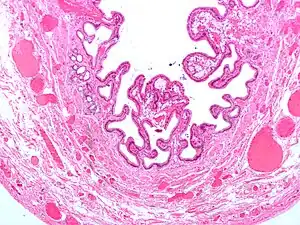

Anatomia Patológica

A vesicula está distendida e avermelhada com exsudado seroso ao exame macroscópico. O lúmen contem por vezes pus ou gases.

Microscopicamente, há aumento da espessura da parede, edema, congestão vascular e infiltrado inflamatório constituído de neutrófilos.

Colecistite crónica

A colecistite crónica resulta da inflamação continua de baixo grau da vesícula, ou de vários ataques autolimitados de colecistite aguda. Microscopicamente o infiltrado inflamatório é constituido por macrófagos, que ingerem as membranas celulares das células destruídas, apresentando-se cheios de lípidos: macrófagos xantelesmizados. Além disso são visíveis seios de Rokitansky-Aschoff: ou evaginações na membrana devido a menor taxa de renovação da mucosa que de destruição. Por vezes à calcificação da mucosa, denominada de vesícula de porcelana: nestes casos o risco de cancro da vesícula é muito mais alto.